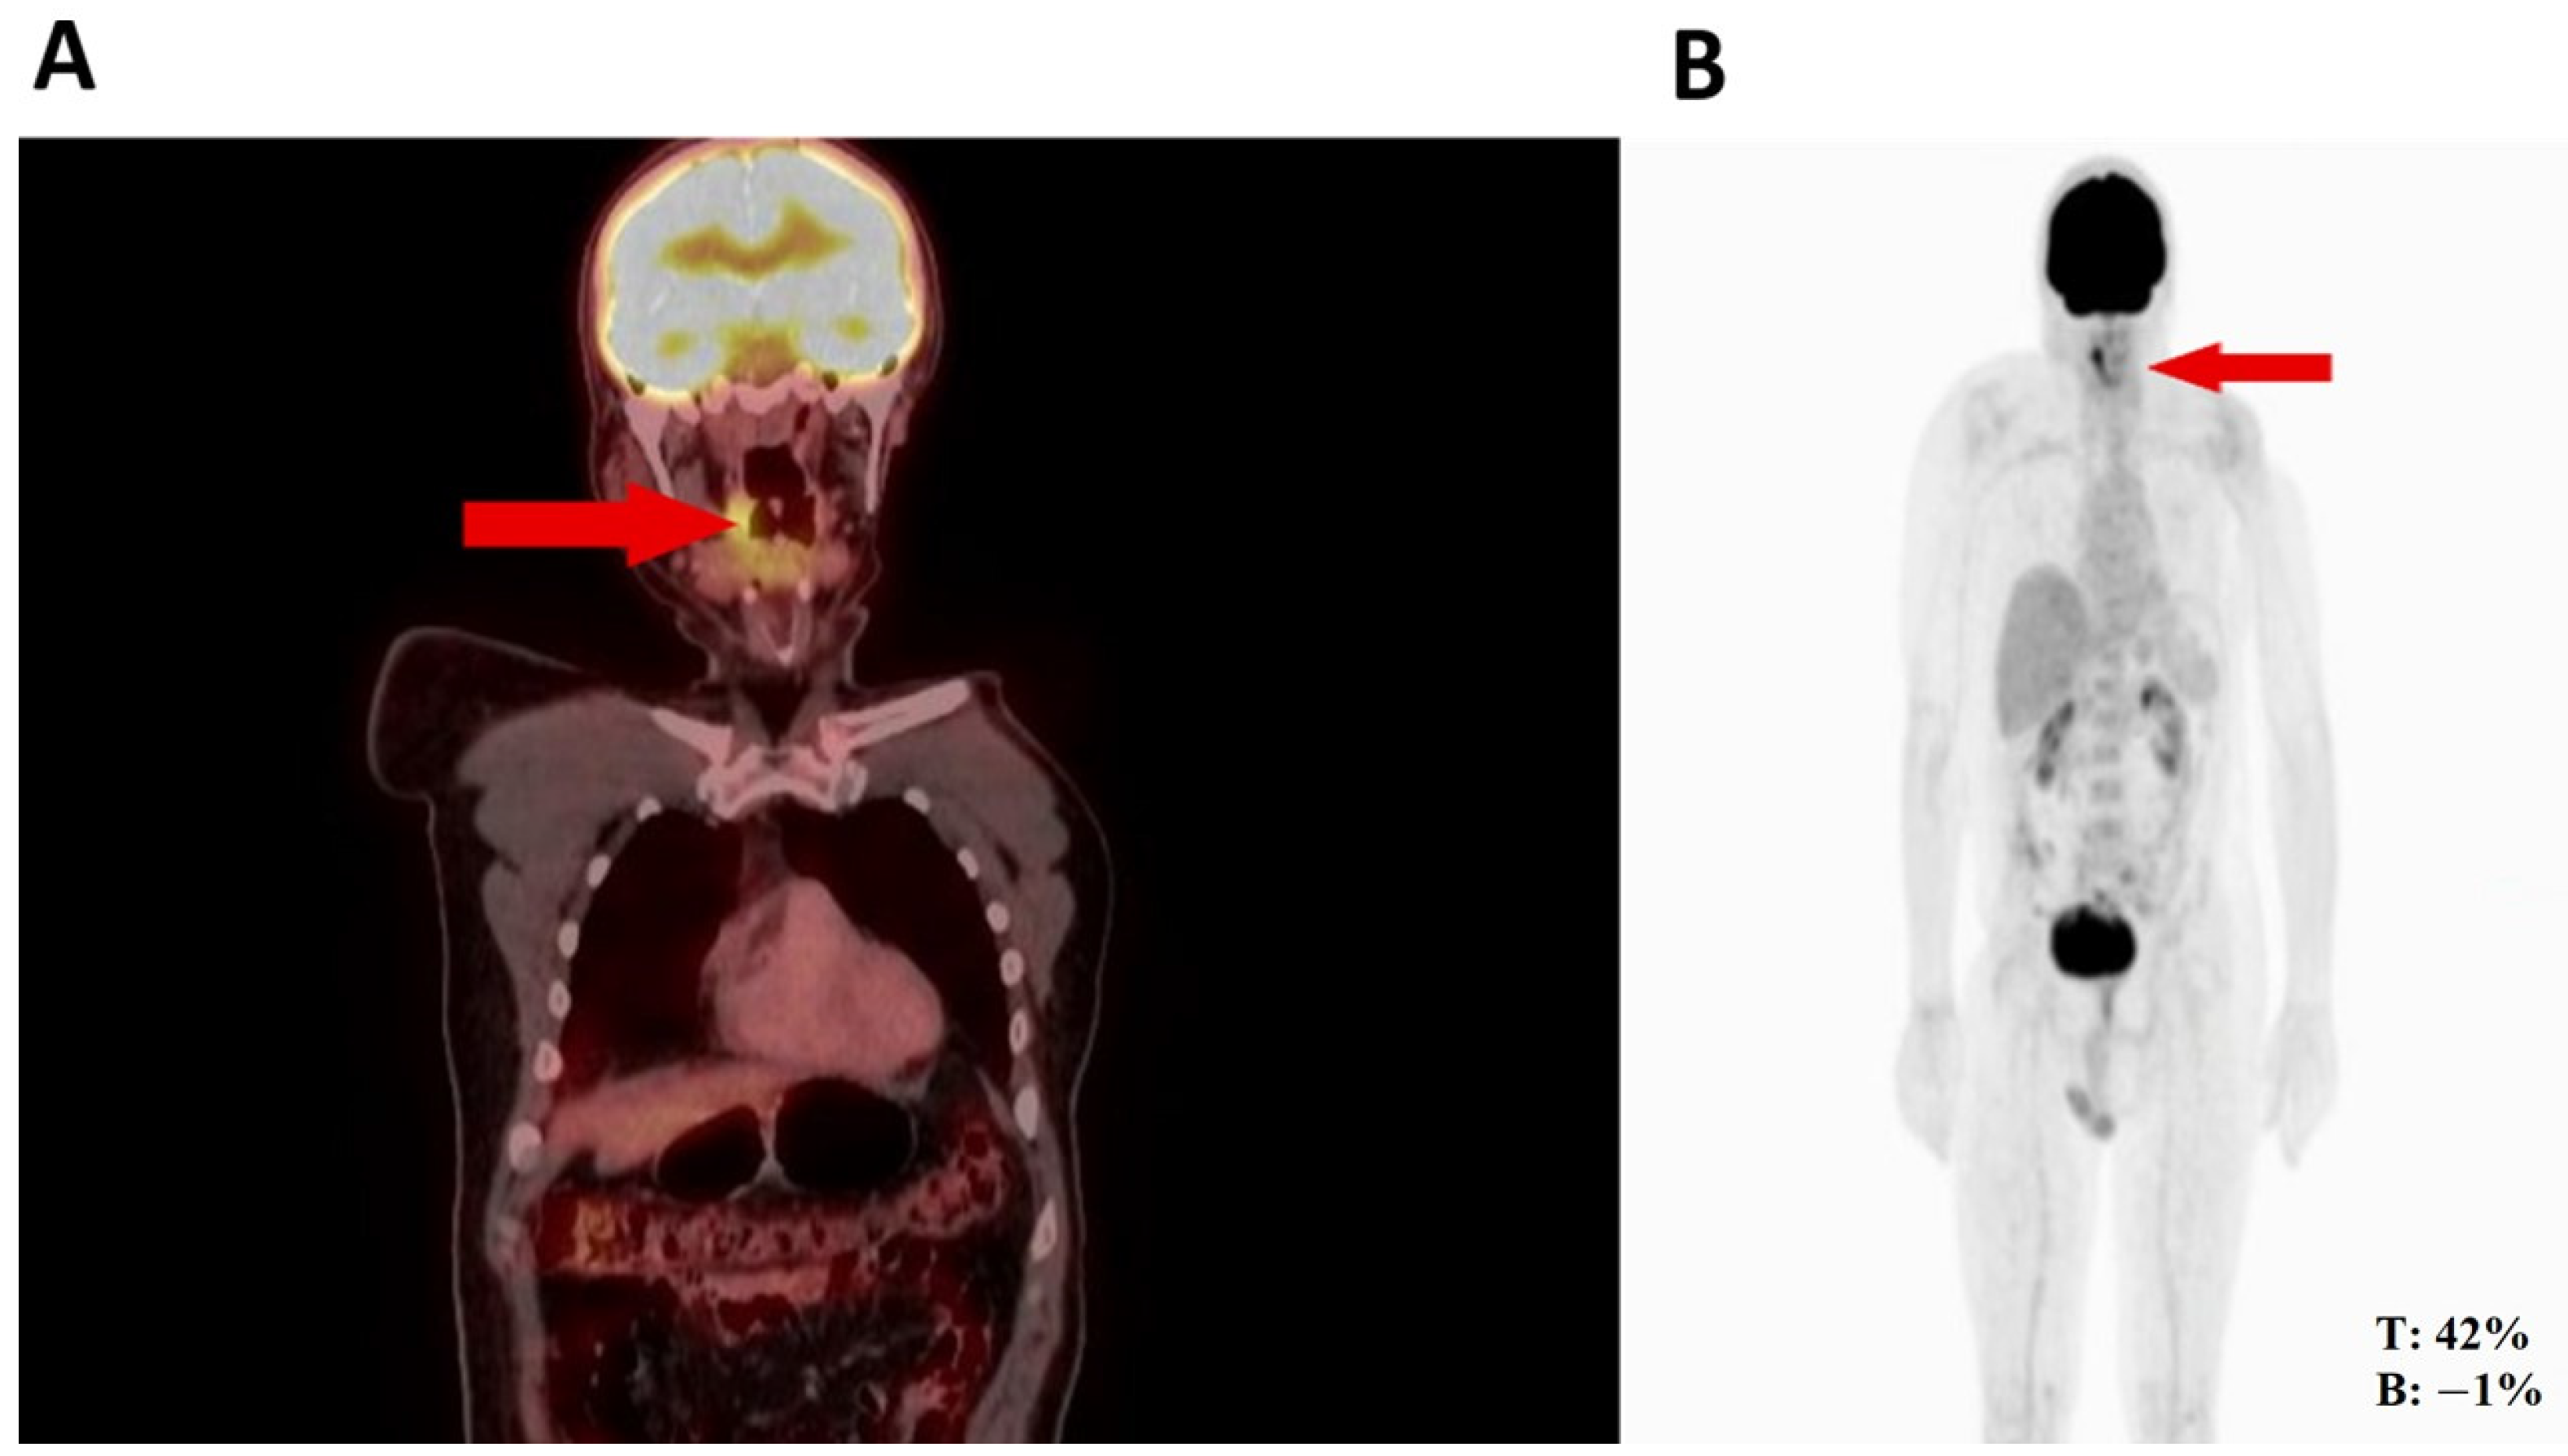

Thus, the orthopedic oncology service requested a PET-CT in August 2022, given its utility for diagnosing high- or low-grade sarcomas. Subsequently, the PET-CT (Figure 1) revealed hypermetabolic nodular thickening on the right lateral pharyngeal wall, which was suspicious of neoplasia. Based on the biopsy and PET-CT findings and history of rhabdomyosarcoma, an evaluation by the head and neck surgery service was indicated for surgical assessment.

Figure 1.

(A) Nodule in the right pharynx and palatoglossal arch measuring 22 × 10 mm, SUV 6.5 (red arrow). (B) Hypermetabolic nodular thickening of the right lateral pharyngeal wall, nonspecific, suspicious of neoplastic involvement (red arrows).